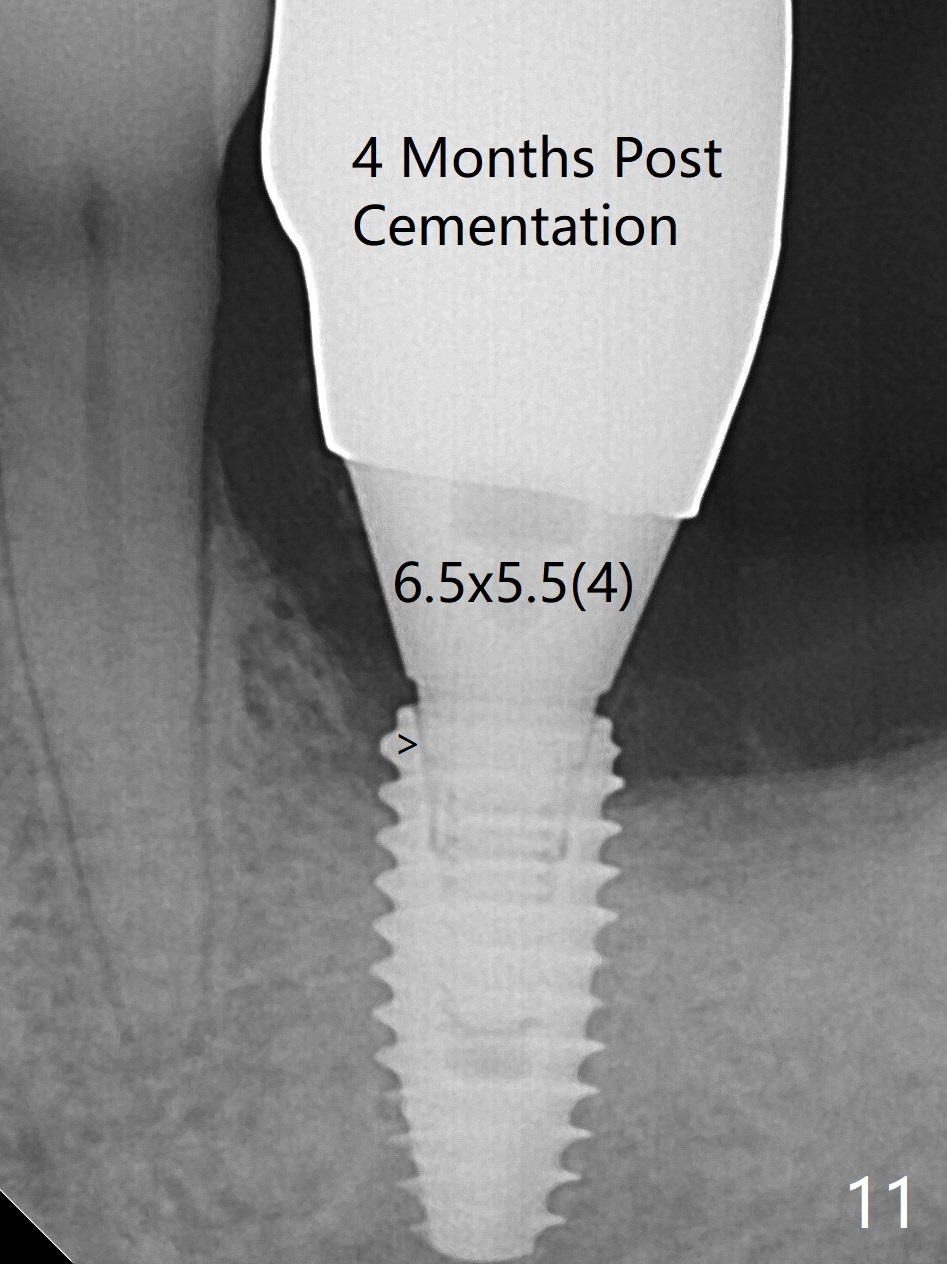

When the patient returns for #19 extraction (Fig.1), there is no 5x10 mm implant available. In fact the smaller one (4.5x10 mm) is able to achieve insertion torque >60 Ncm with more room for autogenous bone/allograft horizontally (Fig.2 *). After insertion of a definitive abutment (6.5x5.5(4) mm), more allograft is placed coronally (Fig.3 *). The gingiva that was between the mesial and distal roots before extraction (Fig.1 *) is transferred distal (Fig.4.5 *). An immediate provisional (Fig.6 P) is fabricated to close the socket opening, followed by periodontal dressing (data not shown). The latter is partially detached 2 weeks postop (Fig.7 D). When it is removed, some of possibly collagen plug is exposed distobuccally (Fig.8). When the plug is removed, some of the bone graft (Fig.9 *) is exposed distal to the provisional (P). New periodontal dressing is applied to keep the exposed graft in place. There is no apparent thread exposure 4 months postop (Fig.10). The abutment is loose 4 months post cementation, probably related to unfavorable crown/implant ratio; but when the abutment is retightened, there is a gap between it and the implant (Fig. 11 >). After relieving the proximal contact of the crown, the abutment is retightened one more time with the same gap (Fig.12 >). In fact the latter is present previously. A narrower abutment with longer cuff appears to be completely seated, probably avoiding contact with the regenerated crestal bone (Fig.13 *). If the new crown gets loose, bury a driver inside the abutment.